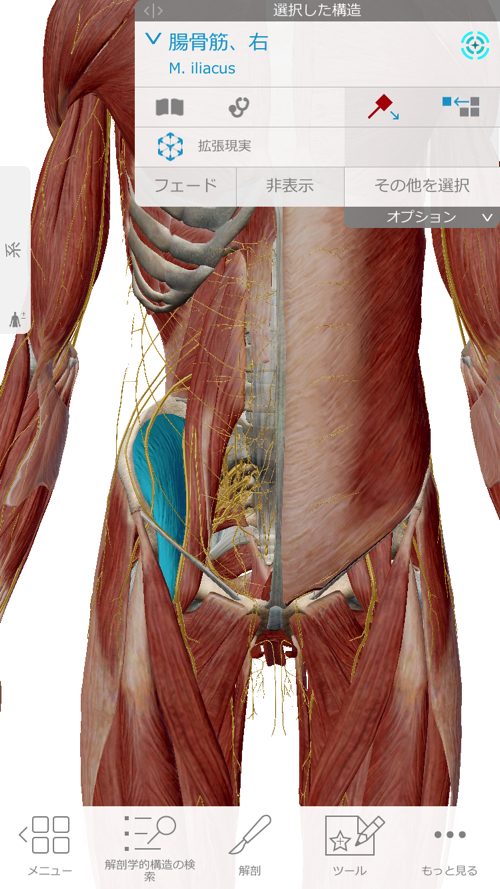

同時にここの腸骨筋なども緩めて鼠径部から膝に余裕を作ります。